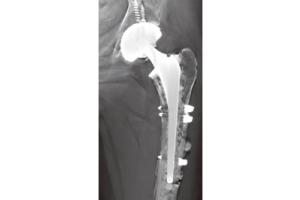

- Лучевая диагностика

Визуализация Shimadzu